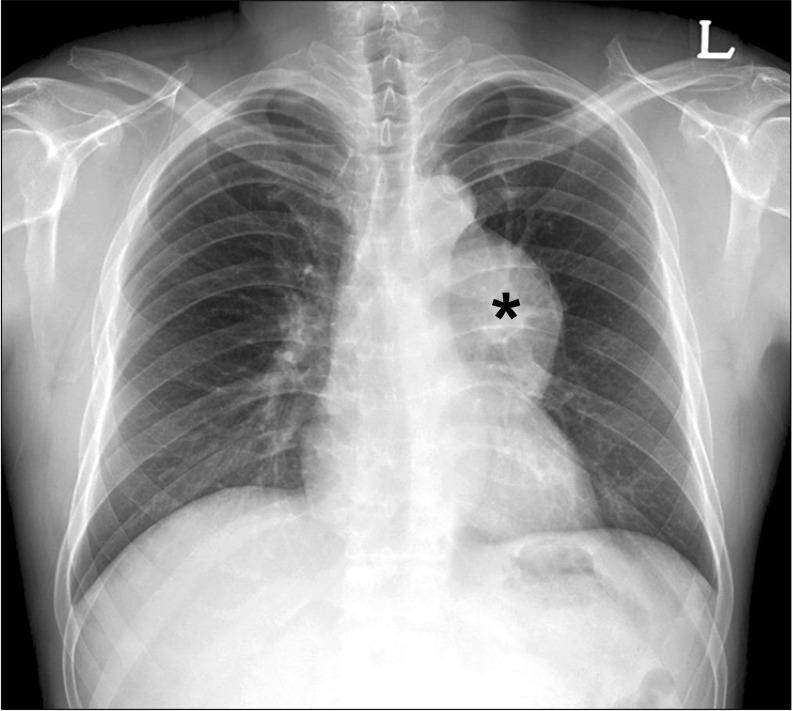

We report a rare case of rhabdomyosarcoma spontaneously arising in an anterior mediastinal teratoma in a 47-year-old male. The patient was found to have an anterior mediastinal mass on a chest X-ray, which was taken two months before his presentation to Asan Medical Center. A subsequent computed tomography scan revealed an 8.9×7.1×8.0 cm heterogeneous mass in the anterior mediastinum. He underwent an excision via median sternotomy. The histopathologic study identified a mature teratoma with embryonal rhabdomyosarcoma.

我们报告了一例罕见的横纹肌肉瘤病例,该肿瘤自发发生于一名47岁男性的前纵隔畸胎瘤内。患者在就诊于峨山医学中心前两个月拍摄的胸部X光片上发现前纵隔有肿块。随后的计算机断层扫描显示前纵隔有一个8.9×7.1×8.0厘米的异质性肿块。他通过正中胸骨切开术进行了切除。组织病理学研究发现是一个伴有胚胎性横纹肌肉瘤的成熟畸胎瘤。